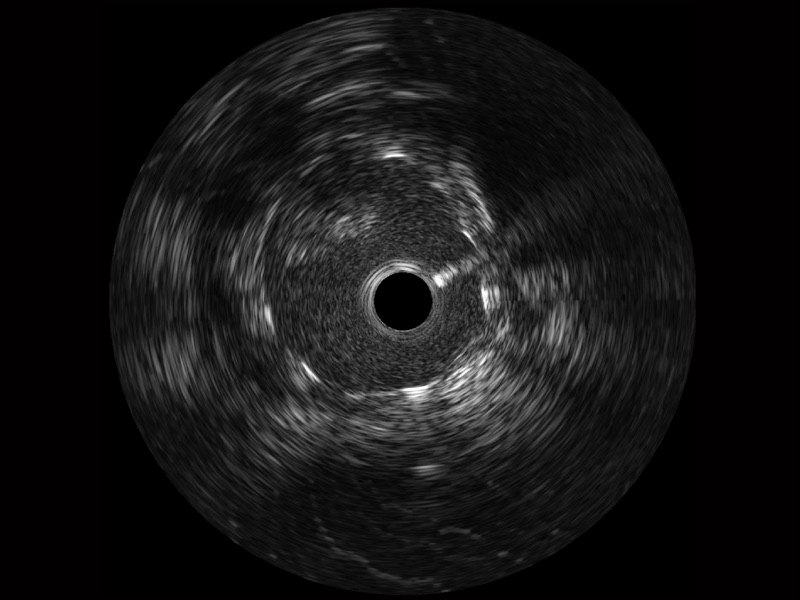

亚星官网宽频IVUS图像

传统IVUS图像

对比传统IVUS导管成像,亚星官网宽频IVUS图像的近场支架梁显影更细腻,远场中膜外血管仍清晰可辨,兼顾远中近,兼顾分辨力与穿透深度